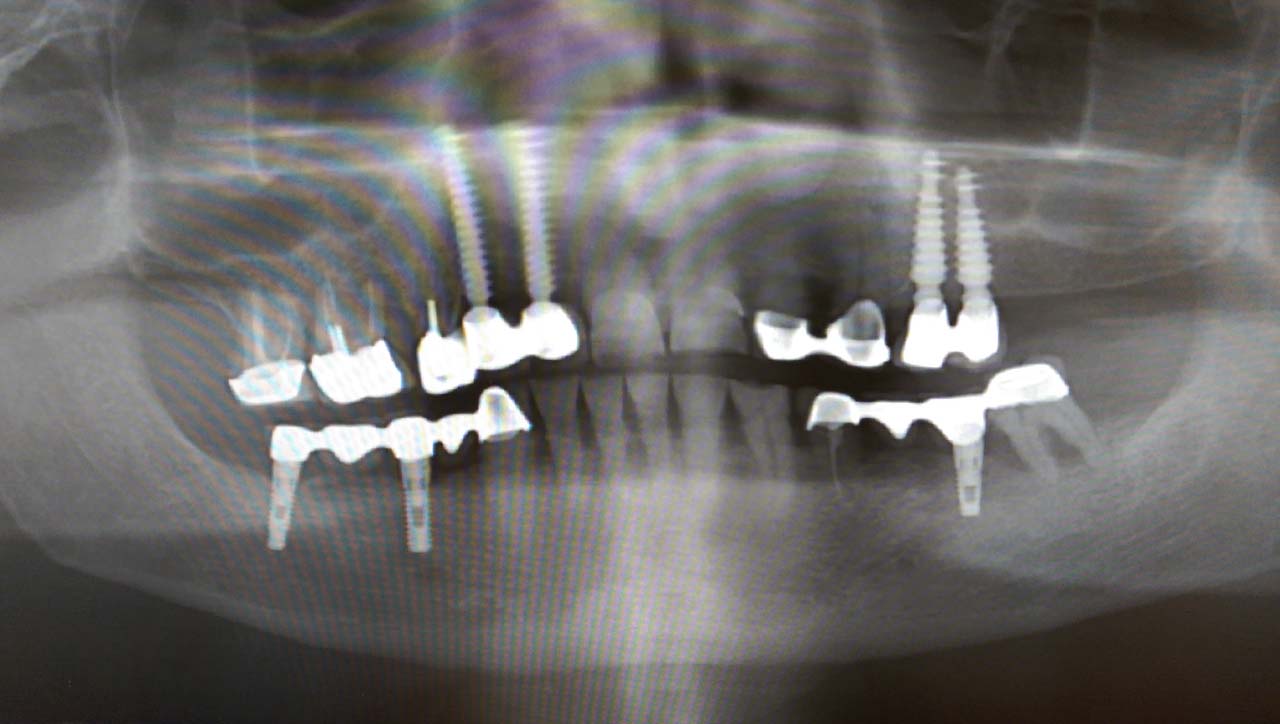

Alsó állcsont teljes rehabilitációja 72 óra alatt, azonnal terhelhető implantátumokkal súlyos paradontitisben szenvedő dohányzó páciens esetében. Az alsó állcsont fogai mind mozogtak az előrehaladott fogágypusztulás miatt.

A fogakat eltávolítottuk, a gyulladt, fertőzött csontot kitakarítottuk, kifertőtlenítettük, majd azonnal implantáltunk.

Svájci, IHDE márkájú, azonnal terhelhető implantátumokat helyzetünk be, és ezekre harmadnapra rögzített, hosszútávú, fémvázas, esztétikus műanyaggal leplezett hidat ragasztottunk be.

Ezt az ideiglenes hidat a sebek gyógyulása miatt használjuk, de tartóssága miatt véglegesként is használható. A legtöbb esetben, ahogy itt is, 6 hónap múlva porcelán hídra cseréljük, a teljes gyógyulás után.